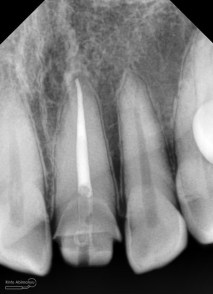

Foto radiografis trial guttap gigi 22

Nah dari foto ronsen ini juga saya melakukan evaluasi hasil pengisian pada gigi 11 21 nya… alhamdulillah pengisian yang kemarin terlihat sepanjang kerja dan padat serta rapat… Pada gigi 22 nya pun pengepasan guttap terlihat sudah sepanjang kerja…

Foto radiografis selesai perawatan saluran akar pada semua gigi

Foto radiografis akhir

Dari foto ronsen terlihat gambaran yang “indah” dari mulai pengisian saluran akar yang rapat dan padat serta gambaran sementasi mahkota yang terlihat homogen….